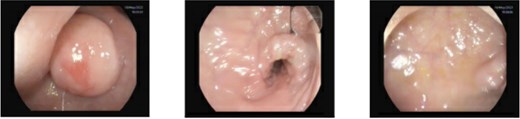

CT scan and colonoscopy revealed a 2-cm submucosal lesion located 23 cm from the anal verge (Fig. 1). Endoscopic ultrasound demonstrated a homogeneously hypoechoic lesion with smooth margins, originating from the muscularis mucosa (Fig. 2). No regional lymphadenopathy was identified. The features were most consistent with a leiomyoma, with gastrointestinal stromal tumour (GIST) considered less likely.

Endoscopic ultrasound demonstrating a homogeneously hypoechoic, smooth-margined lesion arising from the muscularis layer. Endoscopic tattooing for surgical localization, lesion marked at 23 cm from the anal verge with three tattoo spots placed 3 cm distal to the lesion.